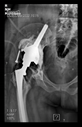

The direction of the cup stem was determined by the guide wire. The aiming device was needed to introduce this wire. After removing the aiming device, the next step was the drilling. Since a cannulated drill bit was used, the previously installed wire could guide the process. A self-positioning reaming tool was then used in the drilled channel. In the prepared cavity, the cup was fitted perfectly. Of the two stemmed cups available to us, the McMinn cup (Waldemar Link, Hamburg, Germany) had the simpler geometry and was therefore chosen. The stemmed cup was inserted according to the manufacturer’s recommendation. In the presence of a significant bone defect, a synthetic bone graft may be impacted for substitution.

The radiological examination allowed us to verify the close bone-to-implant contact and the unchanged position of the implant during follow-up.

In all the cases operated with the above-described targeting procedure, the stems of the cups remained between the cortical bone surfaces without perforation of the linea terminalis, as shown by postoperative radiographs. There were no complicated surgical situations. In 16 cases, the wound healings were uneventful, and the hips were able to bear weight again after postoperative rehabilitation.